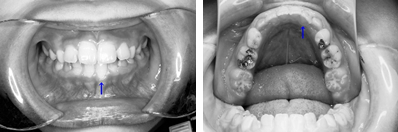

普段のかみ合わせのまま下顎を後ろに押し下げようと力をかけた場合、上顎前歯と下顎前歯がぶつかって上顎まで後ろに下げようとする力が働いてしまいます。そこで、チンキャップを使用する場合には前歯の干渉を避けるためにクリアプレートを併用しました。

1年後(7歳半)の口腔内 下顎前歯が抜け替わりましたが、反対咬合の状態です。

装置使用開始4ヶ月目には反対咬合が解消されています。